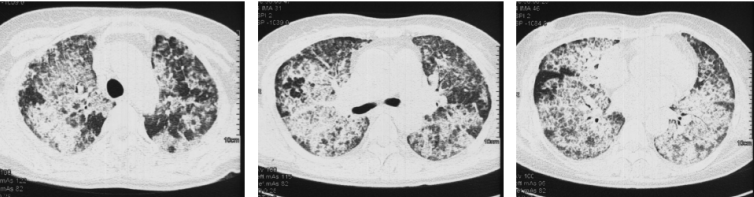

例如文献报道中的Case 3:男性,61岁,2018年3月4日行双肺移植术;移植前3个月曾发生烟曲霉菌感染,应用伏立康唑治疗。移植术后67天出现夜间呼吸困难、伴咳嗽、黄黏痰、双下肢水肿,需应用无创呼吸机辅助呼吸。胸部CT如图19所示。

图片

19  文献报道小囊菌属/帚霉属感染患者的胸部CT

注:A:2018年5月22日胸部CT显示双肺下叶沿气道分布的多发小结节影。B:2018年8月30日胸部CT相对正常。